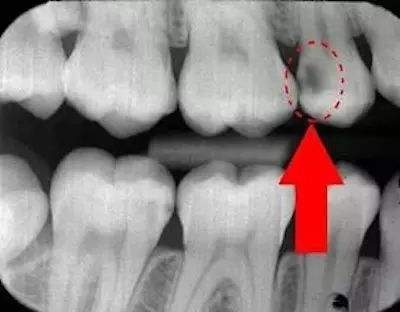

1/ 牙齿的接触面有蛀牙,造成了牙缝变宽。